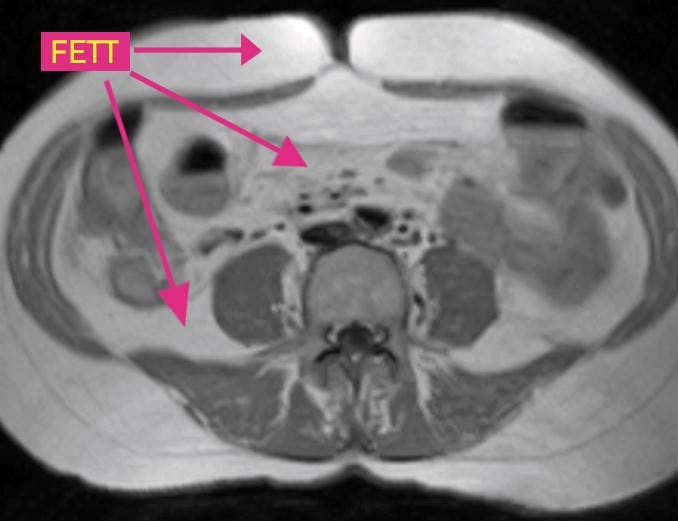

Magefett rett under huden

MAGEFETT RETT UNDER HUDEN Tverrsnitt av mage. Denne personen har en del magefett (det hvite) rett under huden, men har minimalt med fett mellom innvollene.